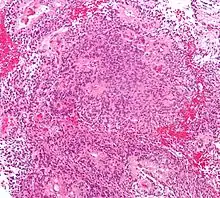

Divers systèmes de catégories ont été proposés dans la littérature au fil du temps pour classer la malignité des astrocytomes. Depuis 1993, le système d'évaluation à quatre niveaux proposé par l' Organisation mondiale de la santé (OMS) est le plus largement utilisé et appliqué. Elle est basée sur quatre caractéristiques histologiques : augmentation de la densité cellulaire, mitose, prolifération endothéliale et nécrose. Par la suite, les astrocytomes de grade I, tels que les astrocytomes pilocytiques, sont généralement d'histologie bénigne. Astrocytomes II. Les grades (diffus) montrent une densité cellulaire accrue comme seule caractéristique histologique et sont des néoplasmes avec un degré d'infiltration inférieur. Les astrocytomes III montrent une mitose importante. grade (anaplasique). Et la prolifération ou la nécrose endothéliale sont observées dans les astrocytomes IV. degrés, les soi-disant glioblastomes.

L'astrocytome anaplasique est une tumeur cérébrale maligne caractérisée par une croissance diffuse, une densité cellulaire accrue et des figures de division nucléaire. Elle est issue d'une population cellulaire spécifique du système nerveux central, les astrocytes. Selon la classification OMS des tumeurs du système nerveux central, la tumeur correspond à une tumeur de grade III.